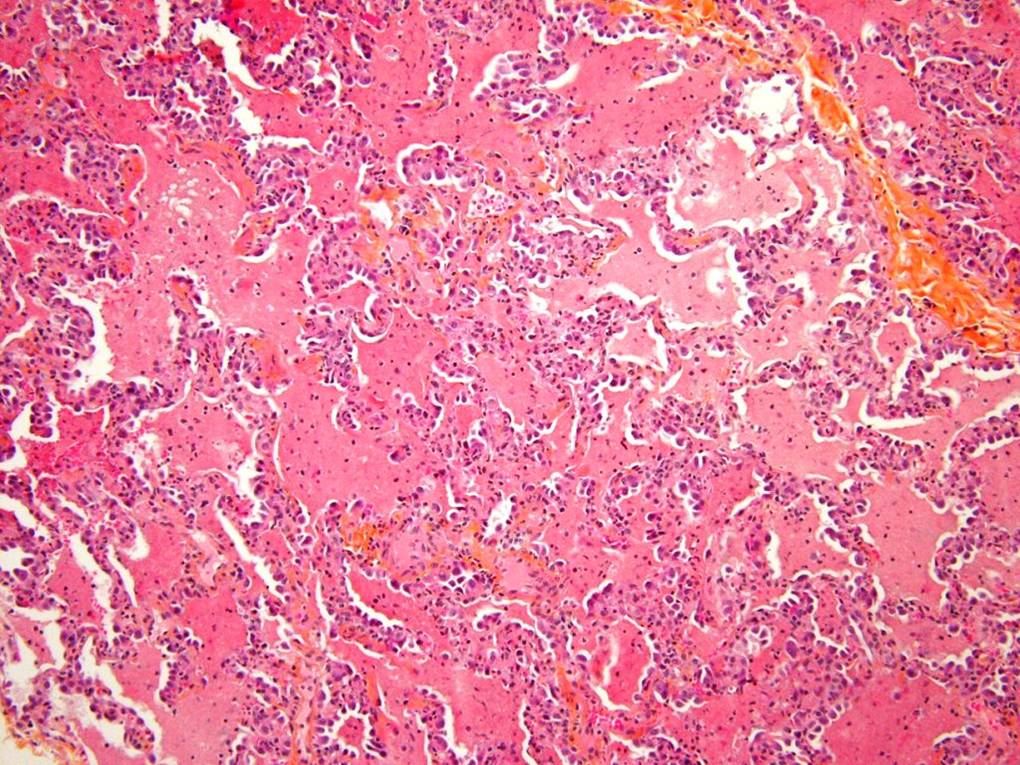

A lung biopsy was performed 24 hours after the steroids were commenced. The biopsy of the right middle lobe and right lower lobe was performed via a right thoracostomy. It was tolerated well with no air leak and no chest tube was required.

Please interpret the histology slides: (The final slide is a Periodic acid Schiff stain (PAS))

| figure 3 | figure 4 | figure 5 |